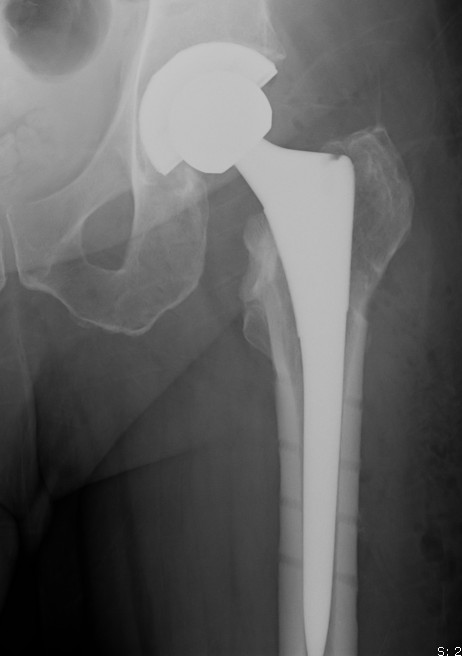

Older patient - arthroplasty

Young patient - valgus osteotomy

- systematic review of salvage THA after failed fixation subcapital fractures

- compared to primary THA for subcapital fractures

- increased risk deep infection, early dislocation and peri-prosthetic fracture with salvage THA